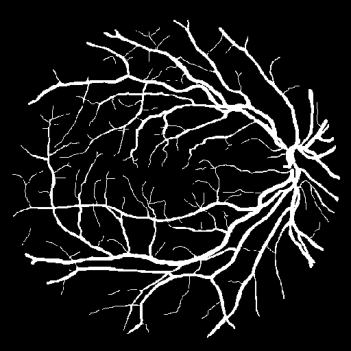

Vessel segmentation is an essential task in many clinical applications. Although supervised methods have achieved state-of-art performance, acquiring expert annotation is laborious and mostly limited for two-dimensional datasets with a small sample size. On the contrary, unsupervised methods rely on handcrafted features to detect tube-like structures such as vessels. However, those methods require complex pipelines involving several hyper-parameters and design choices rendering the procedure sensitive, dataset-specific, and not generalizable. We propose a self-supervised method with a limited number of hyper-parameters that is generalizable across modalities. Our method uses tube-like structure properties, such as connectivity, profile consistency, and bifurcation, to introduce inductive bias into a learning algorithm. To model those properties, we generate a vector field that we refer to as a flow. Our experiments on various public datasets in 2D and 3D show that our method performs better than unsupervised methods while learning useful transferable features from unlabeled data. Unlike generic self-supervised methods, the learned features learn vessel-relevant features that are transferable for supervised approaches, which is essential when the number of annotated data is limited.